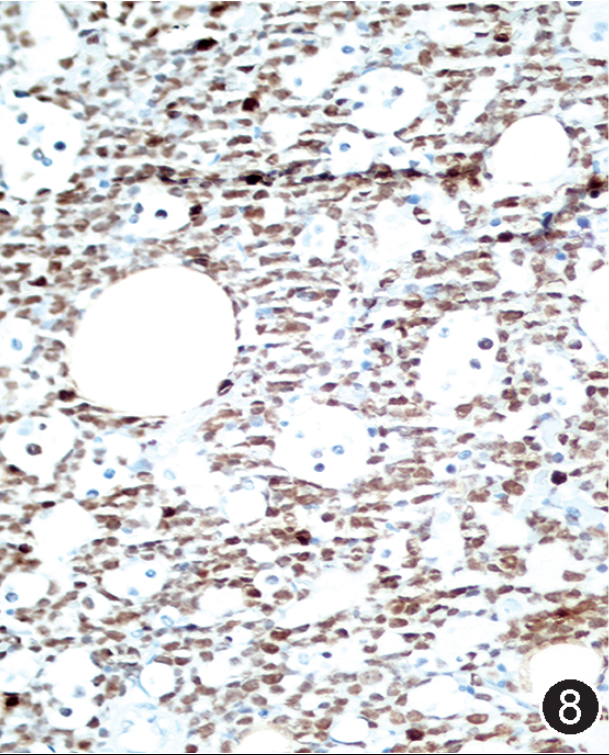

图注:图1 骨髓涂片中的肿瘤细胞(瑞氏染色,×1 000);图2 骨髓活检中的肿瘤细胞(HE, 高倍放大);图3 免疫组织化学染色,CD20部分阳性(EnVision法,中倍放大);图4 免疫组织化学染色,CD19阳性;图5 免疫组织化学染色,CD10阳性;图 6 免疫组织化学染色,MYC阳性,图 7 免疫组织化学染色,bcl-2阴性;图 8 免疫组织化学染色,Ki-67阳性指数约 80%。

根据以上检查结果,需要考虑的淋巴瘤类型包括BL、HGBL、原始细胞标记阴性B-ALL(占B-ALL<5%)以及罕见CD5-CD10+MCL的母细胞变型,须进一步进行免疫组化(包括CyclinD1、CD10、BCL6、MUM1、MYC、BCL2、Ki67)、染色体核型、FISH检测(MYC、BCL2、BCL6、IgH-CCND1)以及白血病融合基因检测加以区分。最终流式细胞学示肿瘤细胞CD38强表达、表达sIgM、sIgD和胞膜Kappa,免疫组化CyclinD1-,细胞遗传学示复杂核型,FISH检测MYC和bcl-6基因重排阳性,白血病52种融合基因阴性,二代测序提示存在TP53、CCND3、MYC、TCF3、FOXO1等HGBL、DLBCL中而非B-ALL/LBL中的常见基因突变类型,因此综合诊断为HGBL伴MYC和bcl-6基因重排。